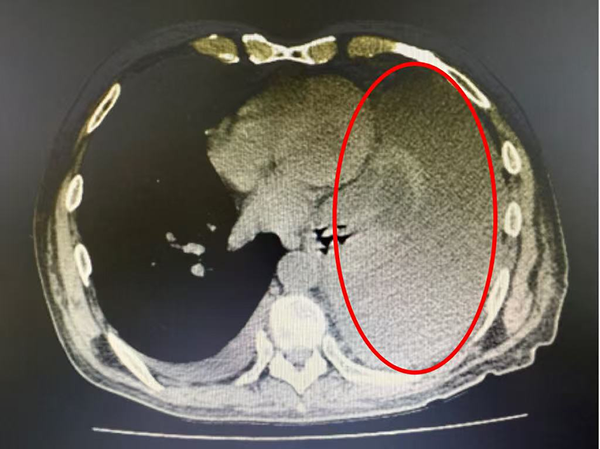

他来到市五院肿瘤内三科时,气短症状已十分严重,左肺完全压缩,纵膈明显右偏,“那段时间就像被困在深水里,连睡觉都要保持半坐姿,稍微平躺就感觉要窒息。”李先生回忆道。

图片1.png

入院时双肺CT